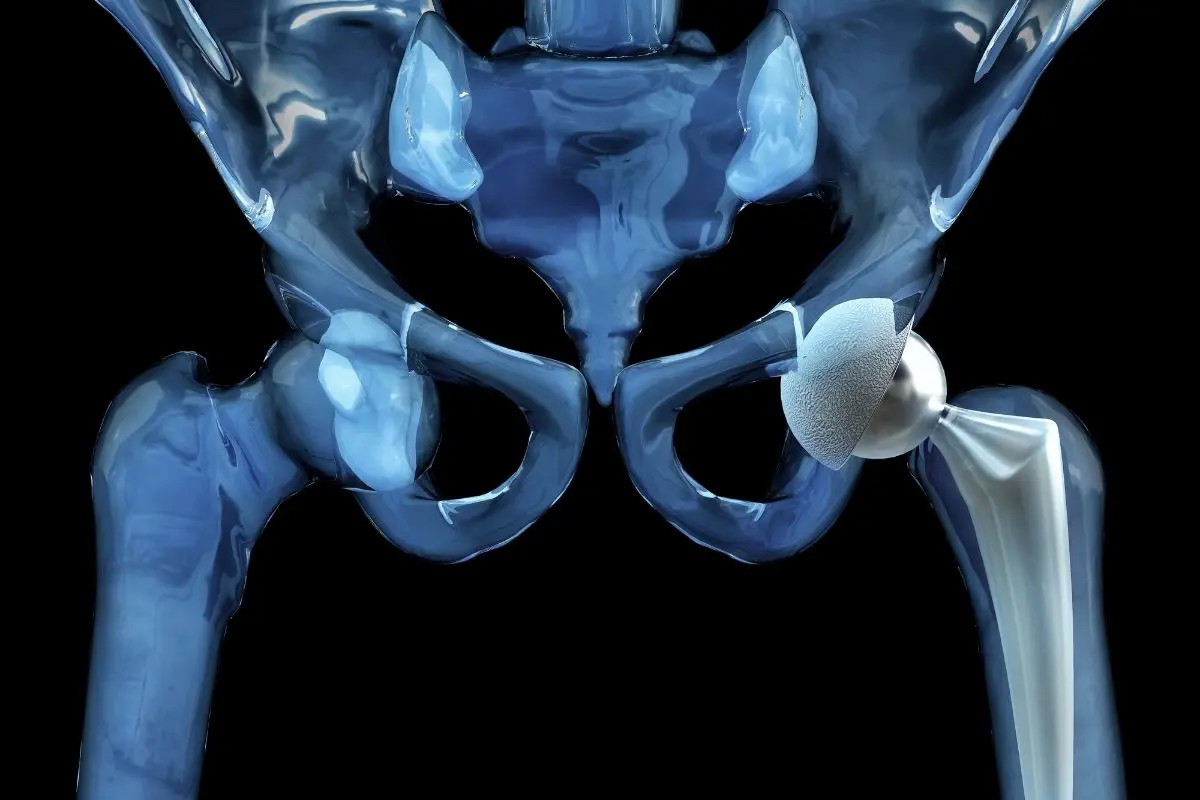

During the surgery, the orthopedic surgeon removes the damaged parts of the hip joint and replaces them with a hip prosthesis made of durable materials such as titanium, ceramic, or medical-grade plastic. These artificial components are designed to replicate the natural movement of the hip, helping patients move more comfortably and with less pain.

The prosthetic hip usually consists of three main components:

- A metal stem placed inside the thigh bone (femur)

- A ball component that replaces the damaged femoral head

- A socket component that replaces the damaged hip socket

These components are made from durable materials such as titanium, ceramic, or medical-grade plastic, allowing the artificial joint to move smoothly and withstand years of use.